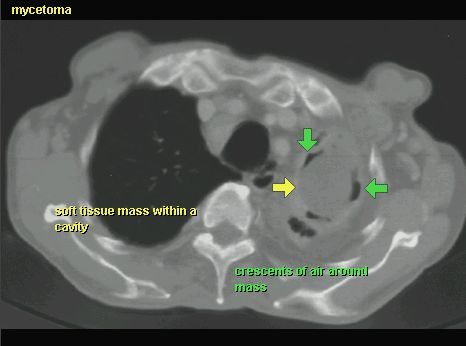

ASPERGILLOZA

TK